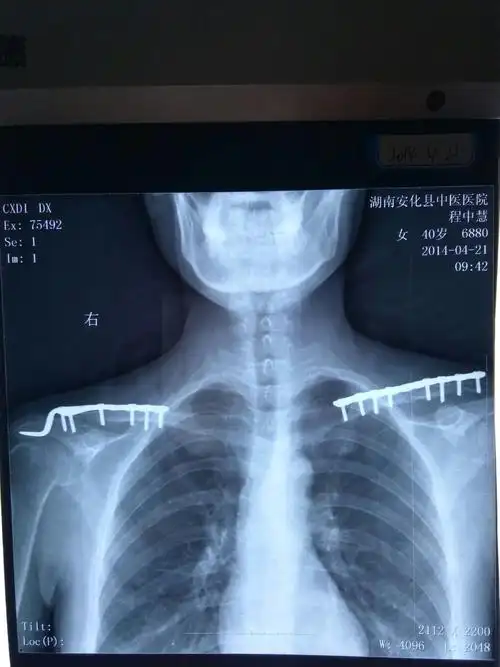

儿童锁骨骨折的治疗

锁骨骨折手术后缝隙过大"一句慢慢会好的"导致五年骨痛,不愈合